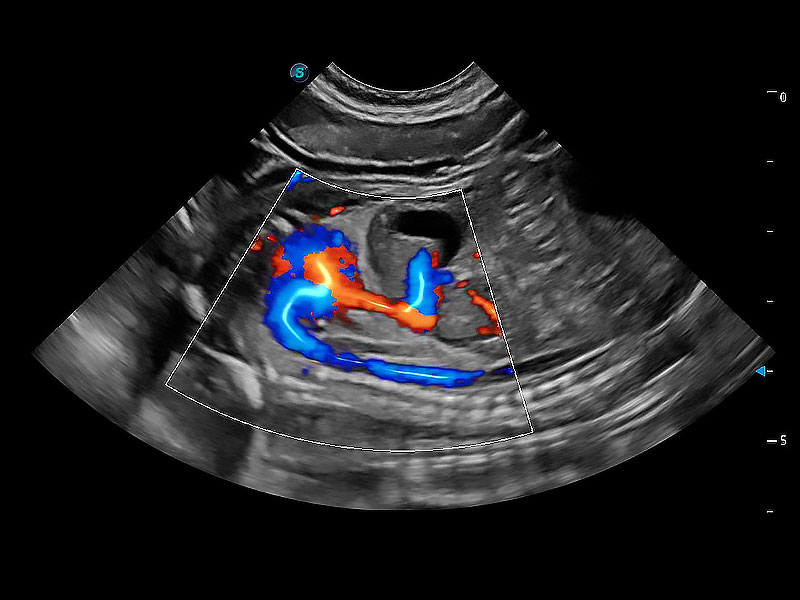

(犬)胎儿主动脉弓立体血流

(犬)二腔心血流